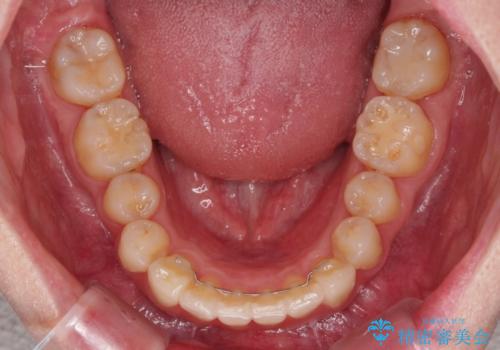

カリエール・ディスタライザーを用いたことで上顎前歯の突出感はスムーズに解消され、歯列不正は1年半ほどでほぼ改善することができました。

しかし、その後インビザライン特有の奥歯がうまく噛めないという問題が長引き、改善に1年近い期間を要することとなりました。